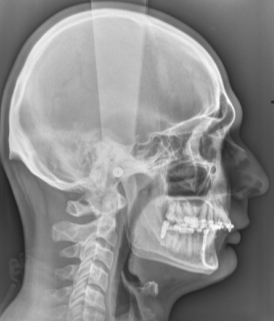

- Pour les téléradiographies, il sera mis dans vos oreilles des embouts métalliques afin que vous soyez parfaitement de profil par rapport à la plaque radiologique et pour vous éviter de bouger. Ces moyens de contention sont totalement indolores. Il vous sera demandé de serrer les dents les plus postérieures et de laisser les lèvres jointes.

TELERADIOGRAPHIES

C’est un examen qui permet de visualiser, en rapport 1/1 (1cm sur le film = 1 cm sur le corps), la tête dans son ensemble en superposant sur un seul film les contours osseux, les dents et les parties molles du visage.

Il est possible de réaliser plusieurs incidences:

a) de profil. C’est l’incidence la plus fréquente.

b) de face,

c) en incidence de Hirtz.

On positionne des embouts métalliques () dans les oreilles afin de nous permettre de vous mettre dans la position souhaitée et de vous aider à la garder et à ne pas bouger.

Cet examen est fait le plus souvent chez l’enfant dans les bilans d’orthodontie.

Il peut être fait également chez l’adulte dans la même indication.

Bilan préchirurgical pour rétrognatisme. La mandibule est en situation trop postérieure par rapport au maxillaire supérieur.